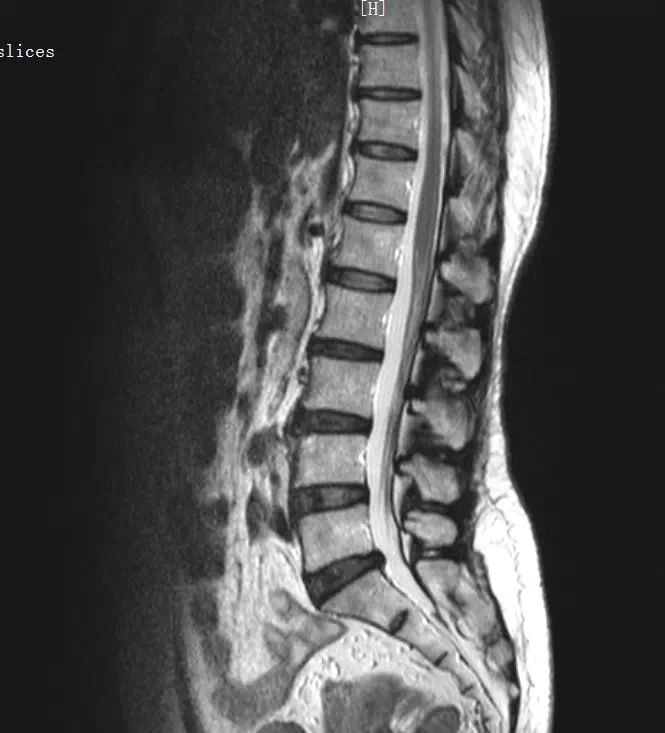

1、腰椎间盘突出症(L4/S1)。

患者腰部生理弧度可,腰部活动度可,腰背部肌张力略高,L4—S1棘间以及椎旁压叩痛(+),以L4—S1左侧为甚,双侧臀上皮神经压痛(+),挺腹试验(-),双直腿抬高试验:(-),加强征(-),梨状肌紧张试验(-),阔筋膜张肌紧张松弛试验(-),双下肢皮肤浅感觉正常,双下肢未见肿胀,双下肢肌力Ⅴ级,膝、跟腱反射(++),巴彬氏征(-)。

西医诊断:1、腰椎间盘突出症(L4/S1) 2、腰椎退行性骨关节病 3、骶尾部筋膜炎 4、腰椎椎间孔镜术后